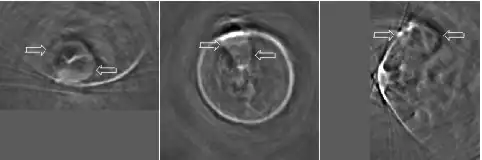

Microwaves have also been used to form 3D thermoacoustic images of the human breast. One of the first devices to do so is depicted in Fig. 10. It consisted of an array of eight waveguides, which directed microwave energy into the breast. A transducer array was rotated in synchrony with the waveguides in order to acquire sufficient data to reconstruct the internal structures of the breast. Figure 11 shows an animation of the typical glandular tissue pattern in a normal breast.